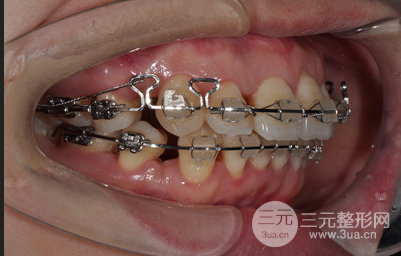

牙齿矫正时间真的太漫长了,在15年做的牙齿矫正,当时还是找的黎主任做的面诊和整个较真过程,一直以来牙齿很不整齐,关键是还有凸嘴的困扰,在面诊之后才知道原来是上下牙列拥挤、上下颌牙弓狭窄、双颌前突,做牙齿矫正是在所难免的了。

对一次缓解拔了四颗智齿,太专业的缓解矫正过程我也说不上来,只知道为了减轻牙齿之间的拥挤程度,不得不拔牙,其实我的凸嘴不算特别严重,在拔牙之后做矫正固定就可以了,但是既然选择了做整形就要做到很好的果,所以在医生的专业保障下做了牙齿正畸,开始了我的漫长牙套之路。